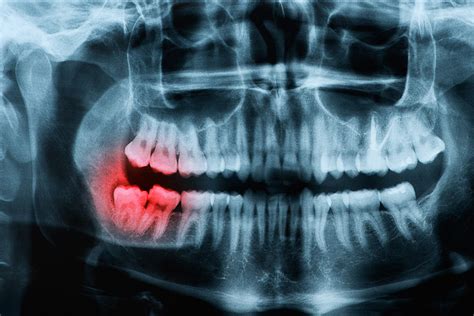

WebRecomendaciones - Cirugía Maxilofacial - Studocu. Recomendaciones para postoperatorio en extracciones recomendaciones después de una limpieza: ms nocomer durante una. WebCentrándonos en lo que debemos comer tras una cirugía maxilofacial, lo recomendable es: Tomar alimentos blandos (cremas, purés, patatas cocidas, arroz.

WebDespués de una operación, usted sentirá algunos efectos secundarios. A veces hay dolor. También puede haber hinchazón e inflamación en el área de la incisión. Su cirujano puede avisarle qué efectos secundarios esperar. También puede haber complicaciones. Hay cosas que no se pueden prever. WebSe hará una dieta individualizada del paciente, siendo de elección variada y adaptada a sus limitaciones tras la cirugía. Se deben realizar unas 5 o 6 tomas al día, en cantidades moderadas. Beber de 2 a 2,5 litros de líquidos al día, incluyendo agua, leche, zumo, u otros líquidos. WebEn la Clínica Birbe de Barcelona, como referentes en cirugía maxilofacial, queremos darte una serie de recomendaciones nutriconales para la recuperación de estas intervenciones quirúrgicas. Podemos distinguir dos tipos de dietas, según la recuperación que necesite el paciente. WebLa cirugía maxilofacial, llamada medicamente ortognática es la mejor intervención que como cirujano maxilofacial puedo recomendar y muchos de mis. WebUna de las preocupaciones más comunes después de la cirugía es el sangrado. La cirugía provoca un aumento del flujo salival que, además de la supuración. WebEsta cirugía, en los casos avanzados, requiere más de 8 horas de quirófano y estancia hospitalaria prolongada. Consejos para recuperarse antes. Se deben seguir. WebPor eso es que cada tanto el paciente debe hacerse lavados con una solución especial y una jeringa. Pero más allá de esto, en medio de la noche llegó lo que más temía:. Web1- Cirugía oral. Tras una cirugía oral como, por ejemplo, colocación de implantes, biopsias o similar, no es necesario aumentar considerablemente la ingesta de.

WebPor eso es que cada tanto el paciente debe hacerse lavados con una solución especial y una jeringa. Pero más allá de esto, en medio de la noche llegó lo que más temía:. Web1- Cirugía oral. Tras una cirugía oral como, por ejemplo, colocación de implantes, biopsias o similar, no es necesario aumentar considerablemente la ingesta de. WebTras la intervención, es necesario realizar una dieta blanda durante los primeros 2-3 días. Una vez se retiren los puntos de sutura de la fenestración, el ortodoncista coloca.